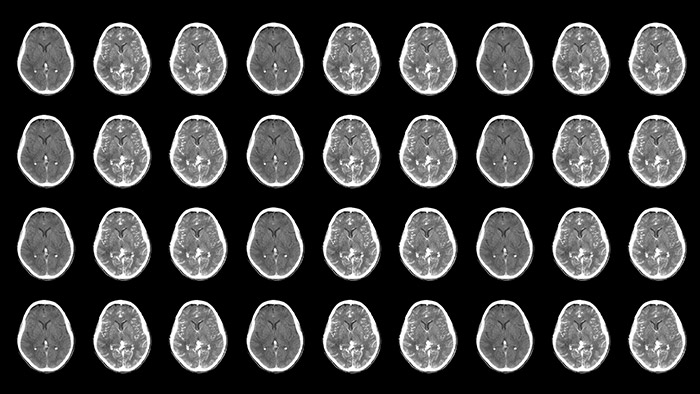

Neurovascular decisions are based on what you see, so see more

Neurovascular care encompasses a remarkable range in approaches to treatment. On one hand, stroke cases are acute and always require immediate treatment for the greatest chance of improving the patient’s quality of life. On the other hand, planned procedures such as complex treatments for aneurysms and arteriovenous malformations (AVMs) need to be meticulously designed and executed to minimize the inherent risk. Neuro suite with SmartCT makes advanced 3D imaging accessible, offering superior workflow with excellent image quality at low dose. Innovative stroke tools, thoughtful collaboration with partners and 24/7 support help you deliver superior neurovascular care.

Improved neuro CT-like cone beam CT images (CBCT) to identify ischemic changes in the Angio suite. The advanced protocol with dual-axis acquisition trajectory and improved reconstruction software results in improved image appearance, compared to conventional CBCT acquisition techniques.

Offers acquisition of two consecutive contrast-enhanced CBCT scans of the brain. In the case of a stroke patient with a suspected large vessel occlusion, this allows the identification of the vessel occlusion in the first phase and the presence of collateral vessels in the second phase.